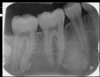

OPG

cone beam CT